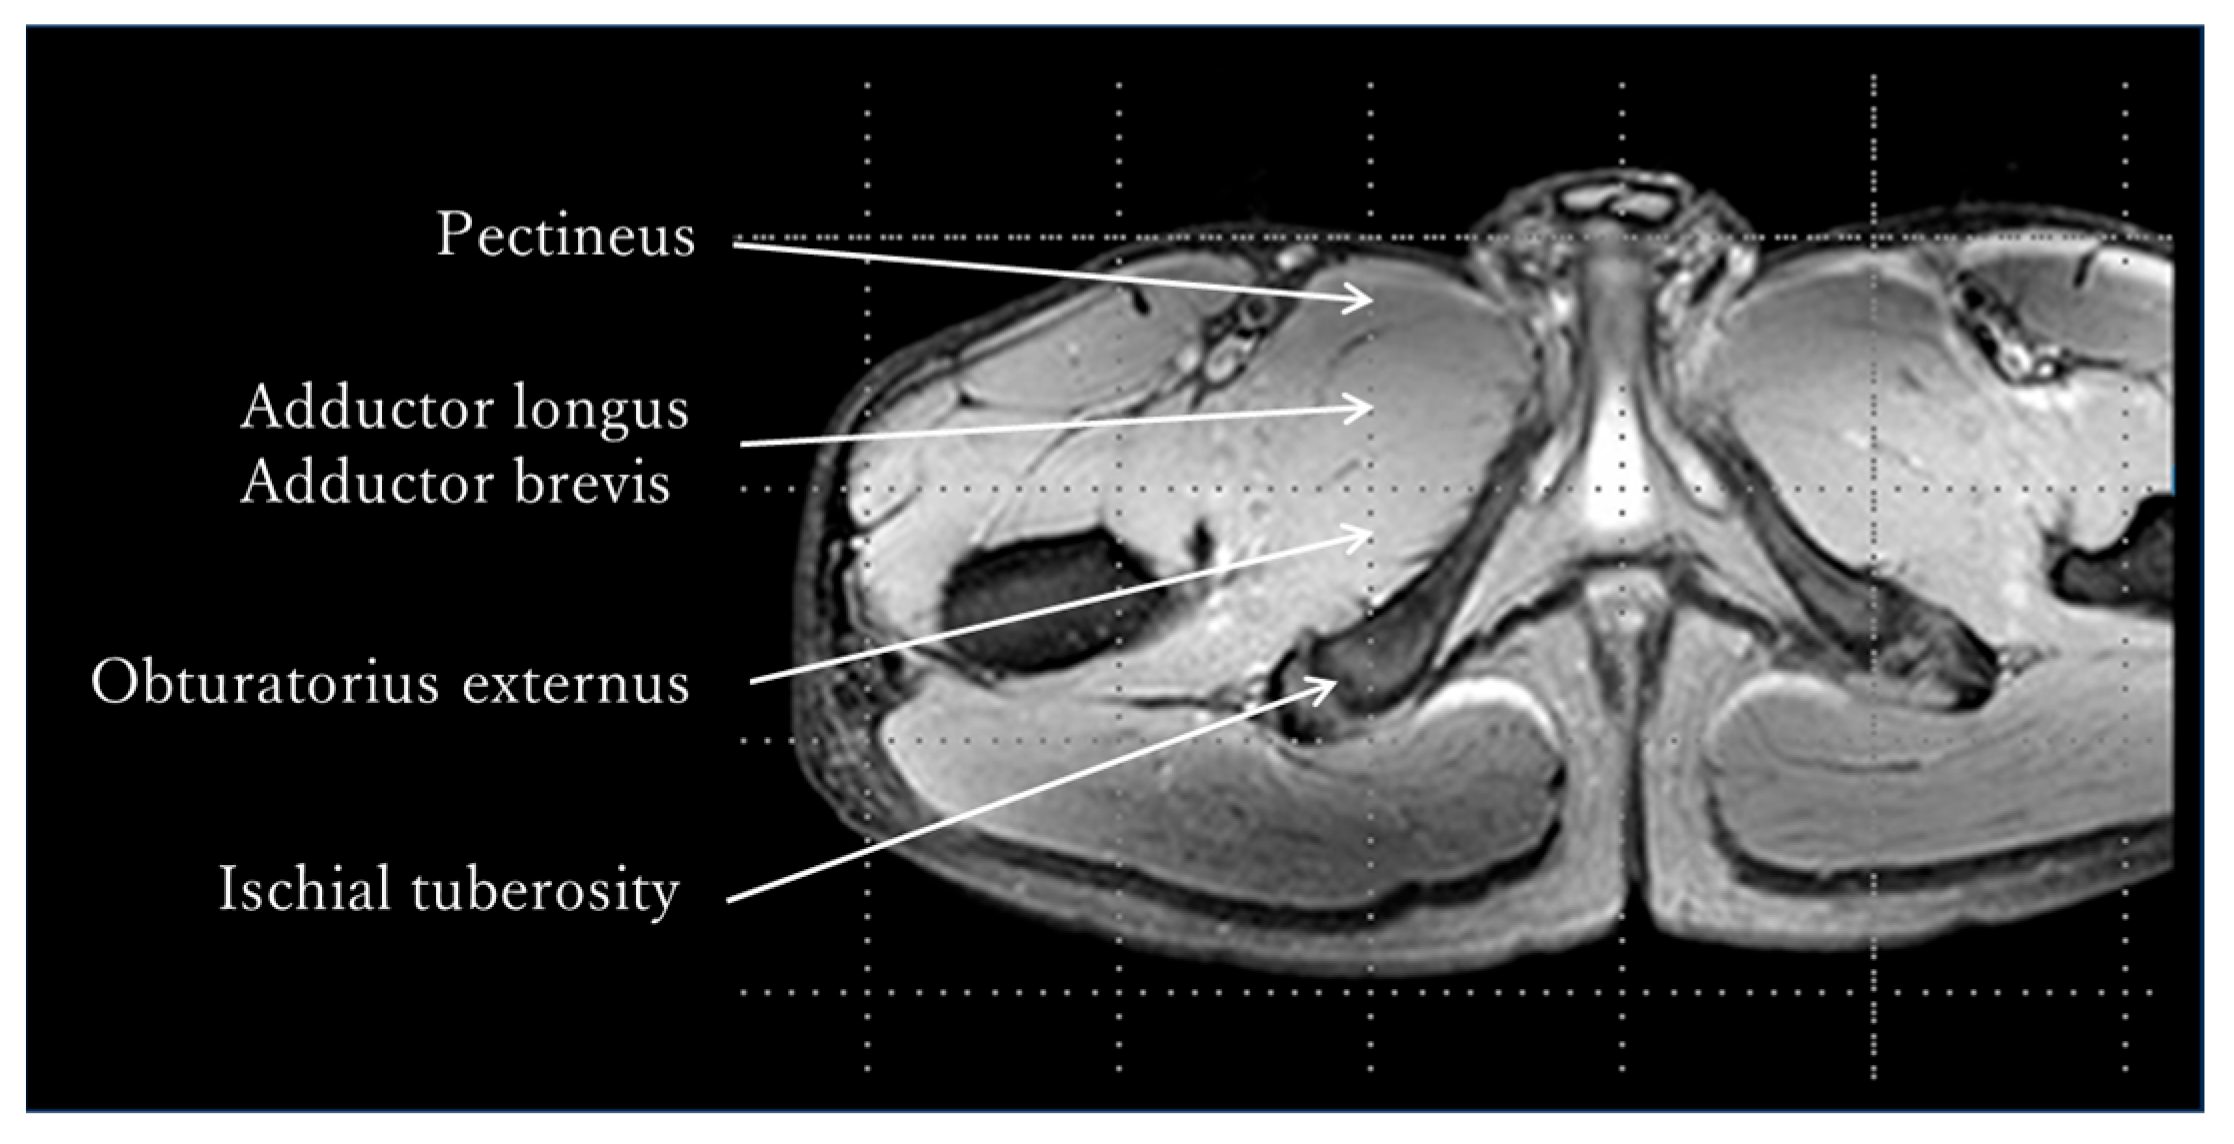

The MRI measurement procedure was as follows: After resting in supine position for 30 min, the adductor muscle group was identified in a transverse section at the tip of the ischial tuberosity using an MRI system (Achieva 3.0T, Philips Medical Systems, Amsterdam, The Netherlands), and pre-exercise T2-weighted images were captured using Multishot’s GraSE method (Figure 2). The limb position for imaging was supine on the imaging table, and the lower limbs were fixed with sandbags so that both hip joints were in a neutral position of adduction and abduction and internal and external rotation. After capturing the pre-exercise images, either internal or external rotation exercises were performed randomly. The adductor muscle group was identified at the tip of the ischial tuberosity as noted above, and post-exercise T2-weighted images were obtained immediately post each exercise. Additionally, a rest period of 30 min or more was provided between the internal and external rotation exercises (Figure 3). The sequence was as follows: matrix, 512 × 512; TR, 3900 ms, TE, 20 ms; slice, 1; slice thickness, 5 mm; echo, 5. The imaging times were 5 min and 28 s, respectively. A T2 map was created from the captured images, regions of interest (ROIs) were set in the pectineus, adductor longus, and brevis, and T2 values were measured using image analysis software MRIcro Version 1.9.1 (http://www.mricro.com; accessed on 13 September 2022) (Figure 4). The adductor longus and brevis were measured in the same ROI because it was sometimes difficult to clearly distinguish them in the images. The Shapiro–Wilk test and F-test were used to assess the normality and variance of the obtained T2 values between the pre- and post-exercise groups. The pre- and post-exercise T2 values, as well as their percent changes, were analyzed using a paired t-test to determine differences in adductor muscle group activity between internal and external rotation exercises. Furthermore, statistical analysis was performed on the effect size (Hedges’ g) and power (1 − β). The reliability of the T2 values was confirmed using the intraclass correlation coefficient (ICC). The ICC (1,1) values were measured twice by a physical therapist with 25 years of experience, whereas the ICC (2,1) values were measured by a physical therapist with 25 years of experience and a research assistant with no experience in skeletal muscle research. Modified R Commander 4.0.2 software (Windows version; https://home.hirosaki-u.ac.jp/pteiki/r/2modrdownload/ accessed on 10 December 2022) was used for the statistical analysis. Experimental data are expressed as mean ± SD.

Figure 2. T2-weighted image. The adductor muscle group was identified in a transverse section at the tip of the ischial tuberosity, and the T2-weighted image was taken pre- and post-exercise using a Philips MRI system (Achieva 3.0T).